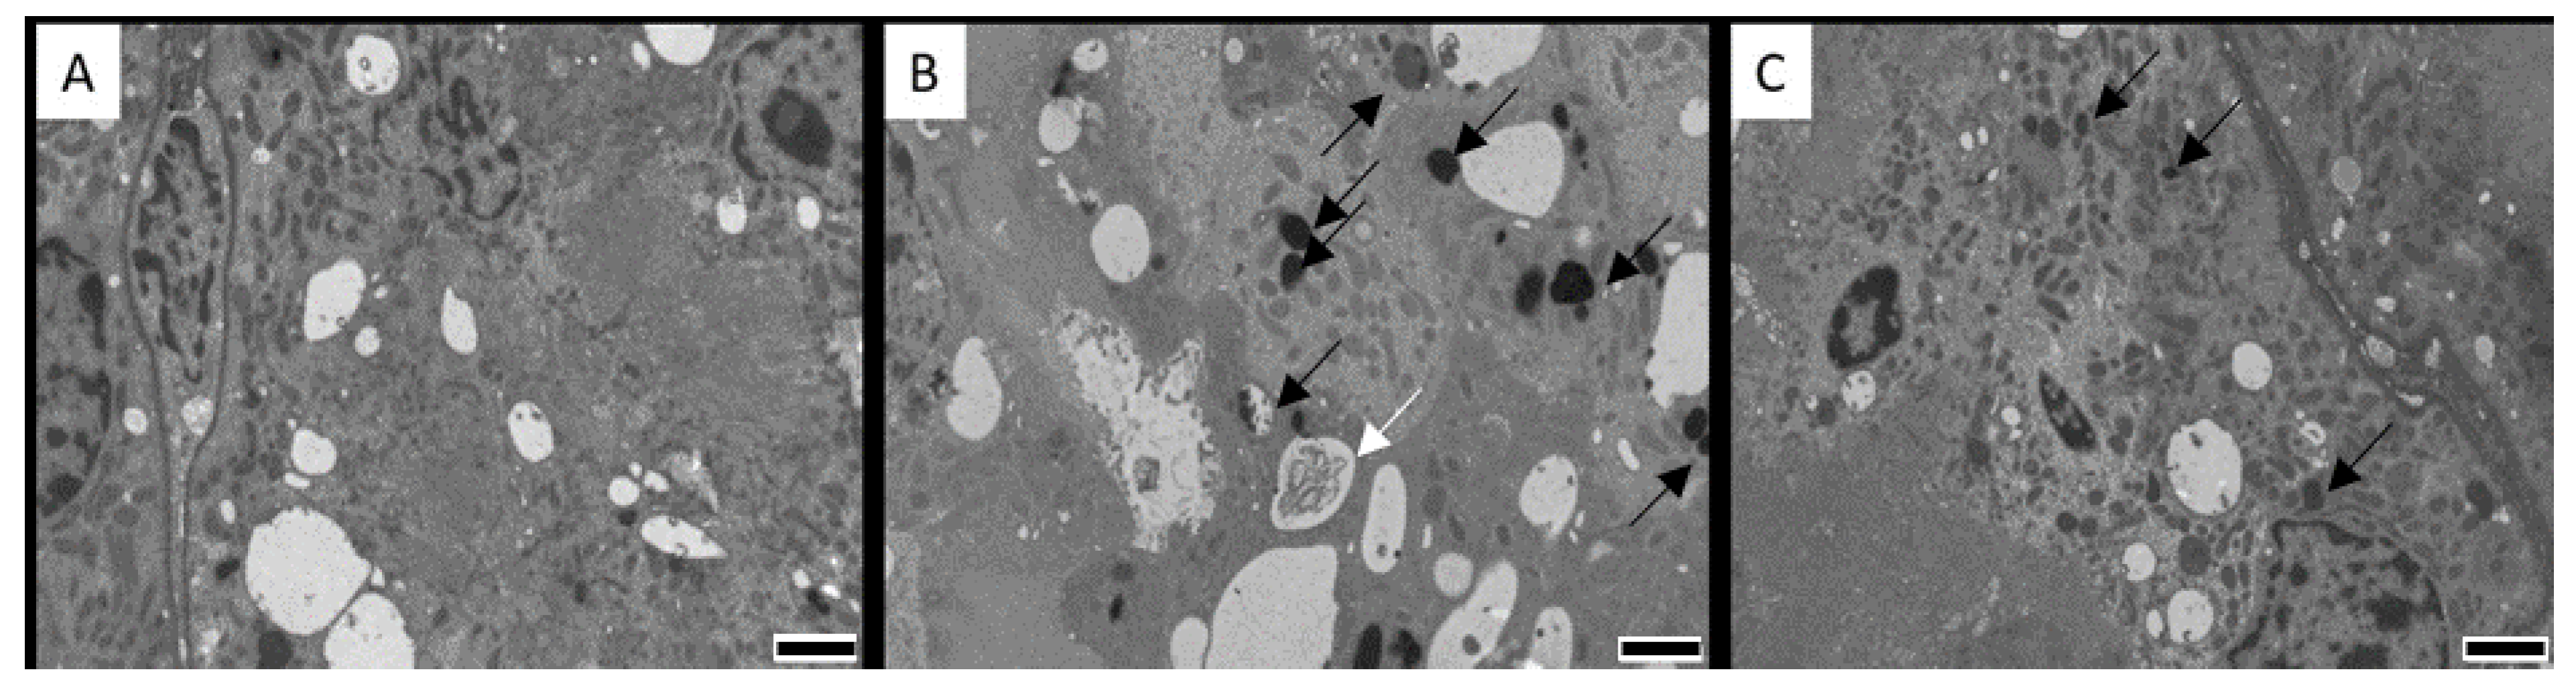

- Brown, T.P.; Manning, R.O.; Fletcher, O.J.; Wyatt, R.D. The individual and combined effects of citrinin and ochratoxin A on renal ultrastructure in layer chicks. Avian Dis. 1986, 30, 191–198. [Google Scholar] [CrossRef]